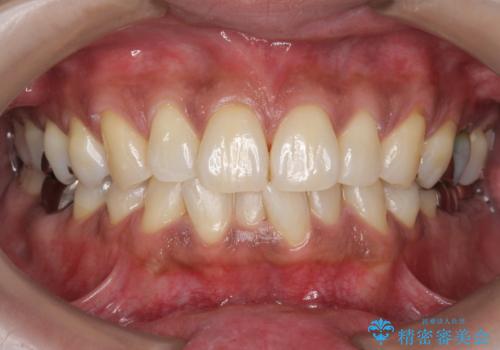

インビザラインでの矯正治療でアタッチメントset前のPMTC

担当医 歯科衛生士